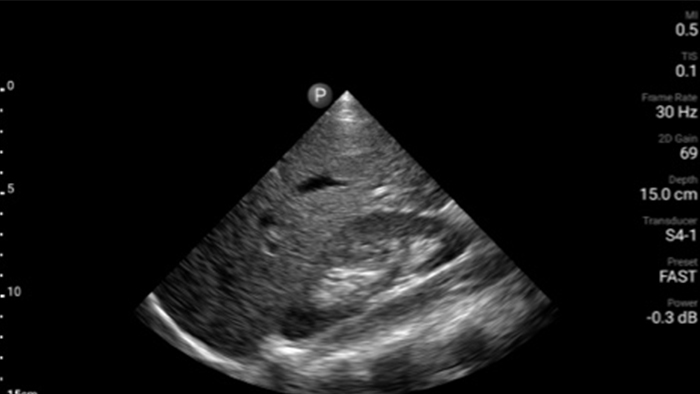

Transductor de disposición en fase de banda ancha Lumify S4-1

• Rango extendido de frecuencias de operación de 4 a 1 MHz • 2D, Doppler a color, Modalidad M, XRES avanzado e imágenes armónicas multivariables • Imagenología de alta resolución para aplicaciones abdominales y cardíacas: optimizaciones de preajustes de imágenes cardíacas, gineco-obstétricas, pulmonares, abdominales y FAST.